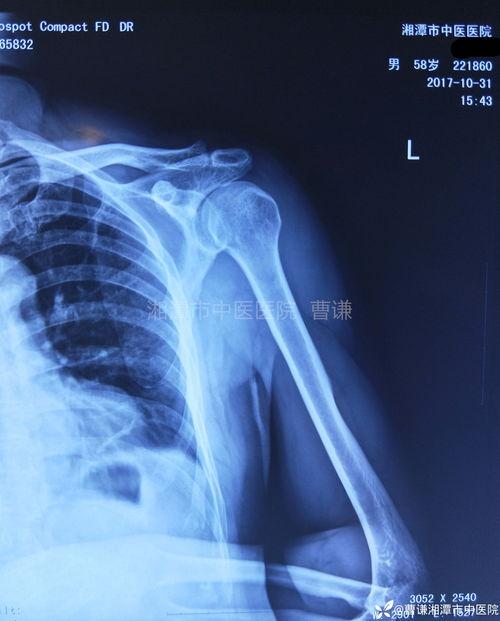

你知道吗,肩关节是人体最灵活的关节之一,但同时也是最容易受伤的关节。当肩关节出现错位或损伤时,疼痛就会找上门来。而肩关节复位视频,就像一把钥匙,能帮你打开疼痛的枷锁。

这些视频通常由专业的康复师或物理治疗师制作,他们会详细讲解肩关节复位的方法和技巧。通过观看这些视频,你不仅可以了解肩关节的结构和功能,还能学会如何正确地复位肩关节,缓解疼痛。